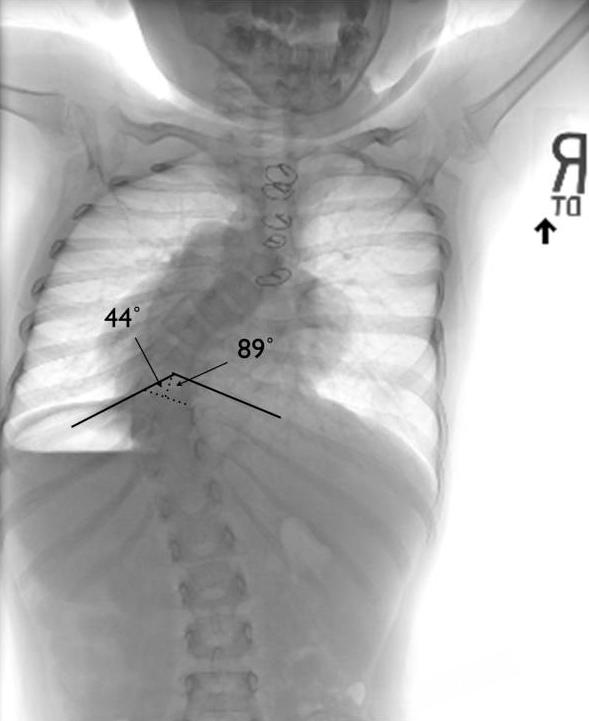

脊柱变形的影响远不止是外形上的改变。研究发现,如果在生长发育期出现明显的脊柱弯曲或畸形,会对胸腔和肺部的发育造成长期影响,容易引发 " 胸廓功能不足 ",从而导致呼吸困难或肺功能下降 [ 8 ] 。此外,脊柱畸形还会影响身高的正常增长,出现身材矮小或生长受限的情况 [ 9 ] 。

x 光片显示,患者由于脊柱变形,对肺部造成了压迫 / [ 8 ]